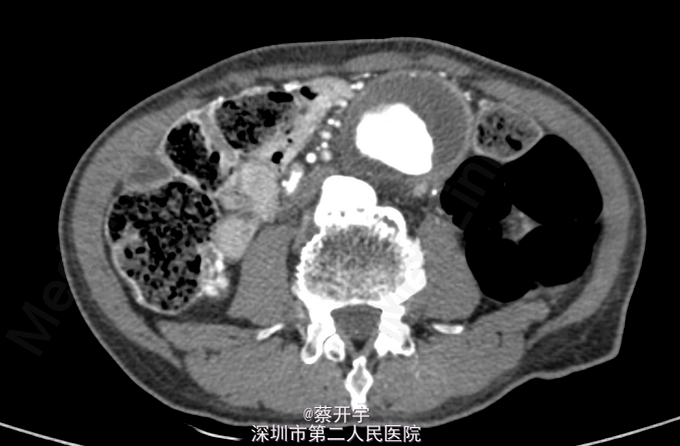

患者,男性,75岁。因“腰背痛20天”入院。 外院腹主动脉CTA示:腹主动脉中下段假性动脉瘤(最宽处57mm),累及右髂总动脉,附壁血栓形成。

查体,心肺查体未见异常。左下腹可触及一搏动性包块,与心率一致,呼吸无相关。 入院完善主动脉全程CTA检查,具体见下图。